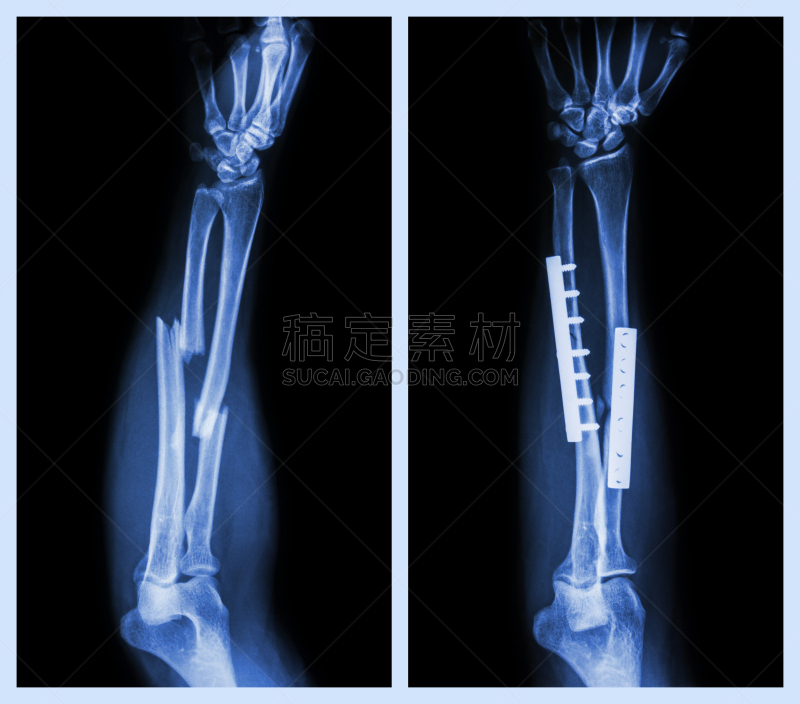

手臂疼痛详情

手臂疼痛详情